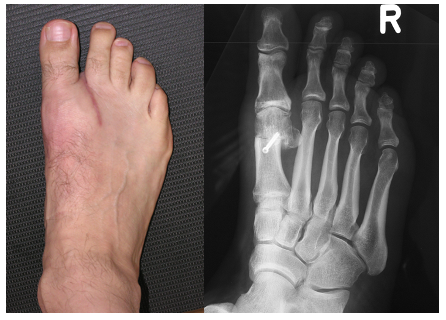

Deutlich sichtbare Exostose vor der Operation

Postoperativ ist der Fuss noch geschwollen, aber die störenden Vorsprünge sind weg und die Beweglichkeit ist sowohl verbessert als auch schmerzfrei.